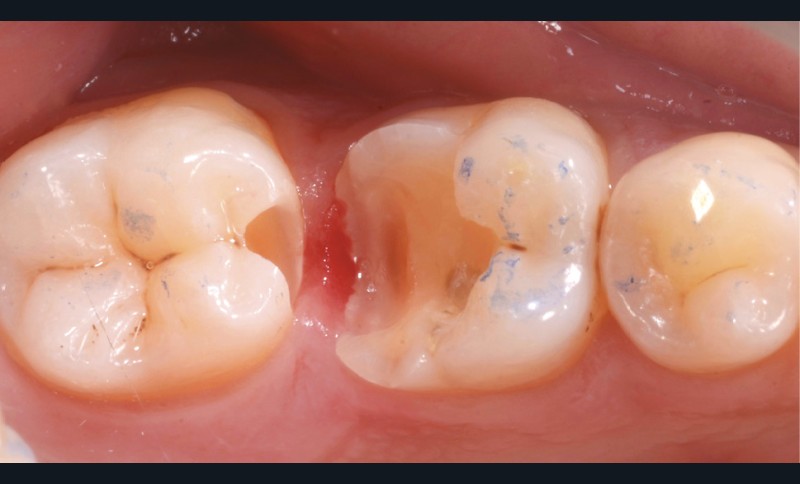

Lors de la préparation d’une cavité pour inlay/onlay, il est fréquent d’être confronté, en fin de nettoyage, à la présence d’une ou plusieurs parois résiduelles dont la résistance mécanique paraît douteuse du fait de leur localisation ou de leur épaisseur. Les parois épaisses (+ de 2 mm) peuvent généralement être conservées (cas clinique 1) et les parois fines (- de 1 mm) doivent généralement être recouvertes. Un inlay (en composite ou en céramique) est alors réalisé. Il doit avoir lui même, au final, une épaisseur globale minimale de 2 mm pour assurer sa résistance mécanique intrinsèque à la mastication. Si un recouvrement cuspidien est indiqué, la réduction occlusale doit donc se faire sur 2 mm de hauteur au minimum [1, 2].

S’il est impossible de connaître avec certitude le risque de fracture d’une cuspide, l’objectif de cet article est de donner des éléments objectifs de prise de décision de la conservation ou du recouvrement des parois d’épaisseur moyenne à la fin du nettoyage cavitaire selon la dent, l’occlusion, la forme et le volume de la cavité, la présence ou non de dentine, la vitalité ainsi que l’incidence esthétique.